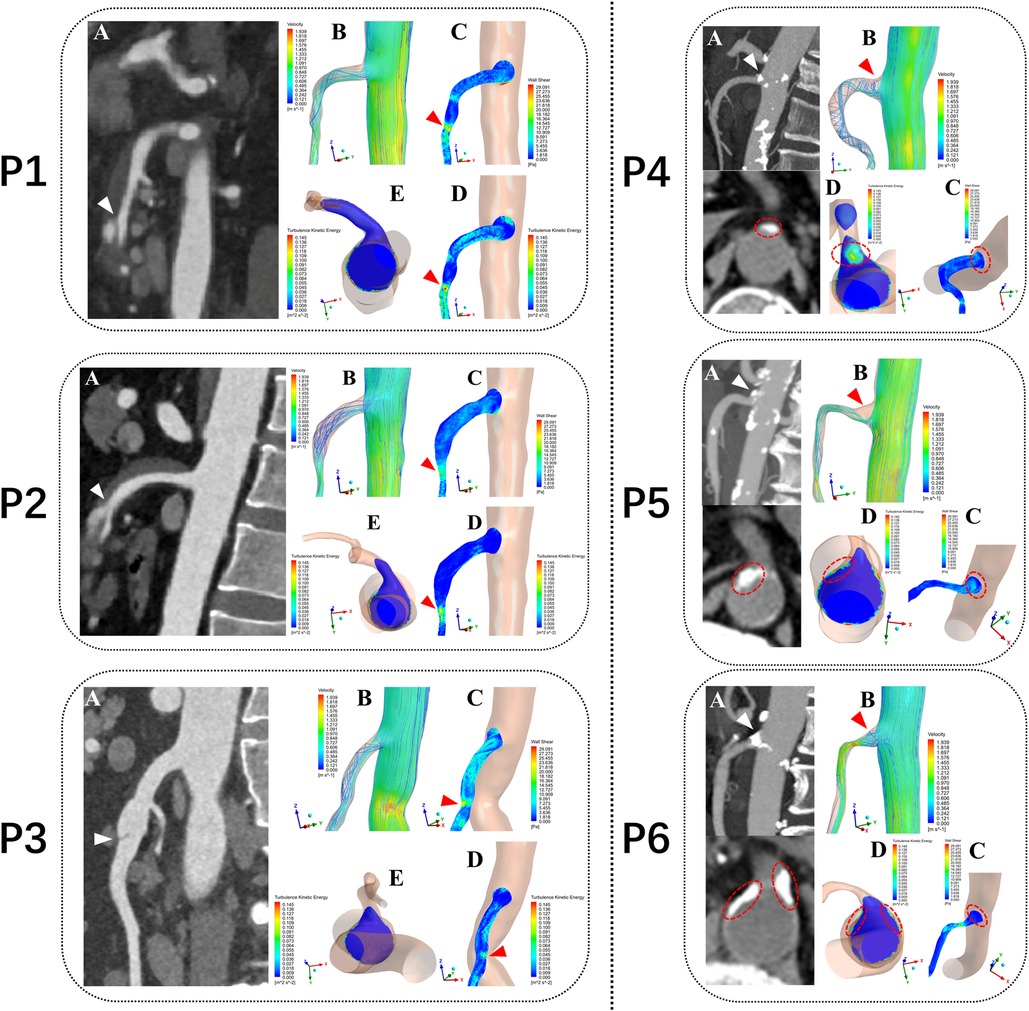

Tetrahedral mesh was divided and the prism layer was created by using ICEM-CFD (Ansys, Canonsburg, PA, USA). Steady-state flow simulations corresponding to the flow conditions at the patient-specific systolic peak were performed using the CFD solver in Fluent (Ansys, Canonsburg, PA, USA) by solving a k-ω SST transition turbulence model (13). Blood was treated as an in compressible Newtonian fluid with a density of 1,045 kg/m3 and a dynamic viscosity of 0.00365 Pa·s (14). For the initial boundary conditions at the vascular openings, we assumed a constant velocity inlet of the patient-specific peak systolic blood flow velocity (cross-section of the abdominal aorta, 5 cm above the SMA ostium) and zero pressure outlet at SMA and cross-section of the abdominal aorta above the common iliac artery for the geometry were applied (15). The mean values of turbulent kinetic energy (TKE), blood flow velocity (BFV), and wall shear stress (WSS) in the three segments of the SMA were then calculated and compared in the 60 patients models. The nephograms of the hemodynamic characteristics in six of them was then displayed: SMAD (P1, P2 and P3), SMAS (P4, P5 and P6) (Figure 3).

Figure 3. Computational fluid dynamics simulation outcomes from six typical patients. P1, P2 and P3 represent three patients with superior mesenteric artery dissection (SMAD), P4, P5 and P6 represent three patients with superior mesenteric atherosclerotic stenosis (SMAS). P1, P2 and P3: (A) Sagittal CT images showing location of the dissections (white arrows). P4, P5 and P6: (A) Sagittal and Axial CT images showing location of the plaques (white arrows). P1–P6: (B) Blood flow velocity (BFV) pattern of the superior mesenteric artery (SMA). (C) Wall shear stress (WSS) distribution at the wall of the SMA. (D,E) Turbulent kinetic energy (TKE) distribution at the wall of the superior mesenteric artery (SMA) (E in P1–P3) and cross-sectional plane at the SMA root (E in P1–P3 and D in P4–P6). red arrows and circles represent the hemodynamic abnormality regions.

In the 6 SMA models (P1 to P6), the regions of high TKE were mainly distributed around the SMA root and almost overlapped with the low BFV vortex regions. In the curved segment of the SMA, the regions of high TKE and BFV coexisted below the anterior convex wall of the SMA. The distribution of high WSS was consistent with the dissection origin (P1 to P3). The high TKE and low BFV regions at the SMA root were consistent with the location of plaques (P4 to P6). An annular low WSS zone appeared at the root of the SMA, whereas the WSS level in the anterior convex wall of the SMA curve was substantially increased. Flow recirculation was observed below the anterior and side walls of the SMA root (Figure 3).